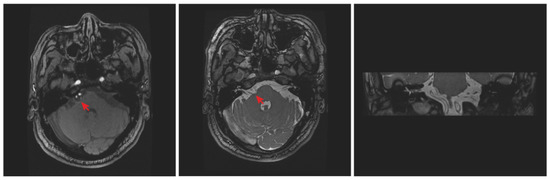

2. Case Report